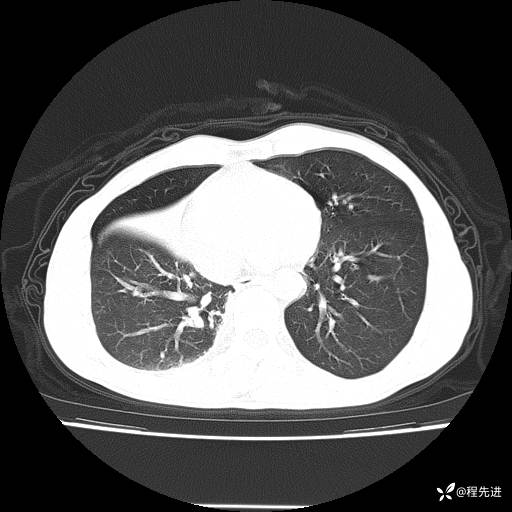

患者性别:男

患者年龄:49岁

主诉:咳嗽、胸痛1周

简要病史:1周前受凉感冒后开始出现咳嗽症状,阵发性连声咳,痰多,黄白痰,不易咳出,伴胸痛、气紧、胸闷,右侧为主,活动用力、呼吸时胸痛明显,曾在当地诊所贴敷膏药仍疼痛

体格检查:T:36.3 ℃ P:80 次/分 R:20 次/分 BP:120/88 mmHg,指脉氧饱和度97%,意识清晰,呼吸平稳,右侧第二、三肋骨压痛,可见膏药贴敷,皮肤无异常,双肺呼吸音粗,未闻及干湿性啰音。心率80次/分,节律整齐,无杂音。腹平软,全腹无压痛无反跳痛

临床诊断:社区获得性肺炎

CT平扫: